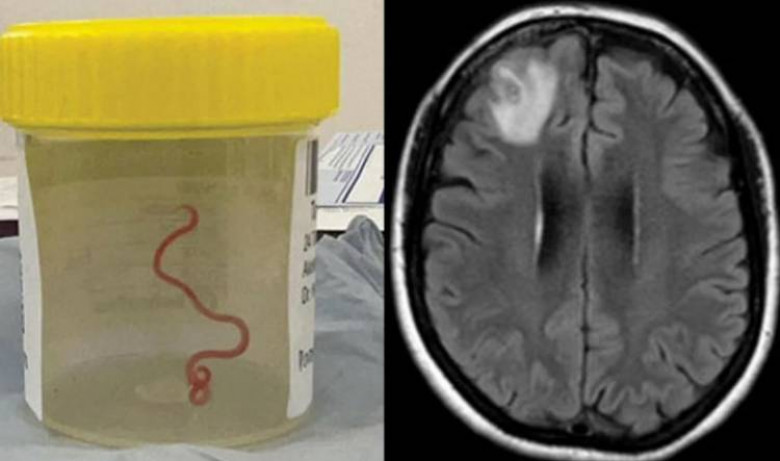

SkyNews-ի փոխանցմամբ՝ մոռացկոտությամբ ու դեպրեսիայով տառապող կնոջ ուղեղից 8 սմ երկարությամբ մակաբույծ որդ են հանել։

Նրա ուղեղի ՄՌՏ-ն ցույց է տվել, որ ախտահարված աջ ճակատային բլթում ապրում է շարժուն հելմինթը՝ մակաբույծ կլոր որդը: Վիրահատությունը միակ տարբերակն էր, և բժիշկները հաջողությամբ հեռացրել են 8 սմ երկարությամբ և 1 մմ տրամագծով կլոր որդը: